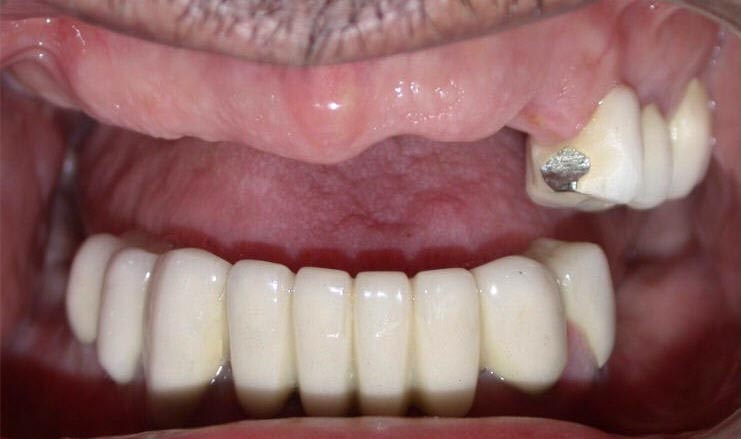

After

Zirconia bridge on Southern DC Implants

Tooth Replacement